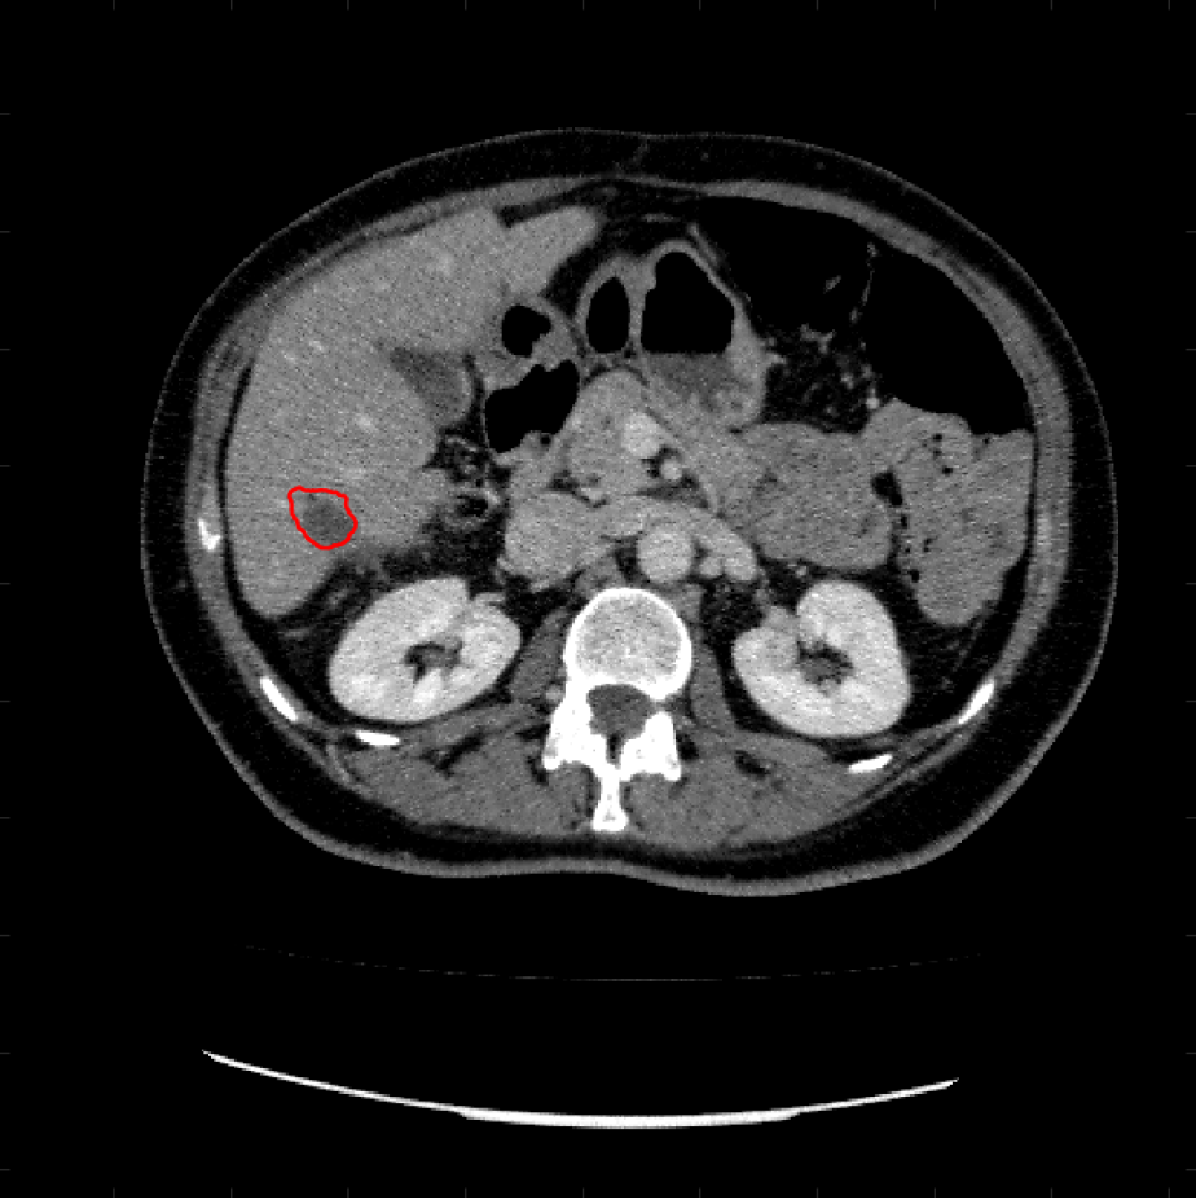

Figure 5: A sample result on the Liver data. We display the input image with the user input \mathcal{M}, the ground truth (GT) and results from the four methods. Moreover, we show comparisons with the model (4) solved in a variational framework with both Total Variation (TV) and Euler Elastica as explicit regularisation, as well as a comparison with the model solved in a Deep Image Prior framework.

Figure 6: A sample result on the Liver data. We display the input image with the user input \mathcal{M}, the ground truth (GT) and results from the four methods. Moreover, we show comparisons with the model (4) solved in a variational framework with both Total Variation (TV) and Euler Elastica as explicit regularisation, as well as a comparison with the model solved in a Deep Image Prior framework.